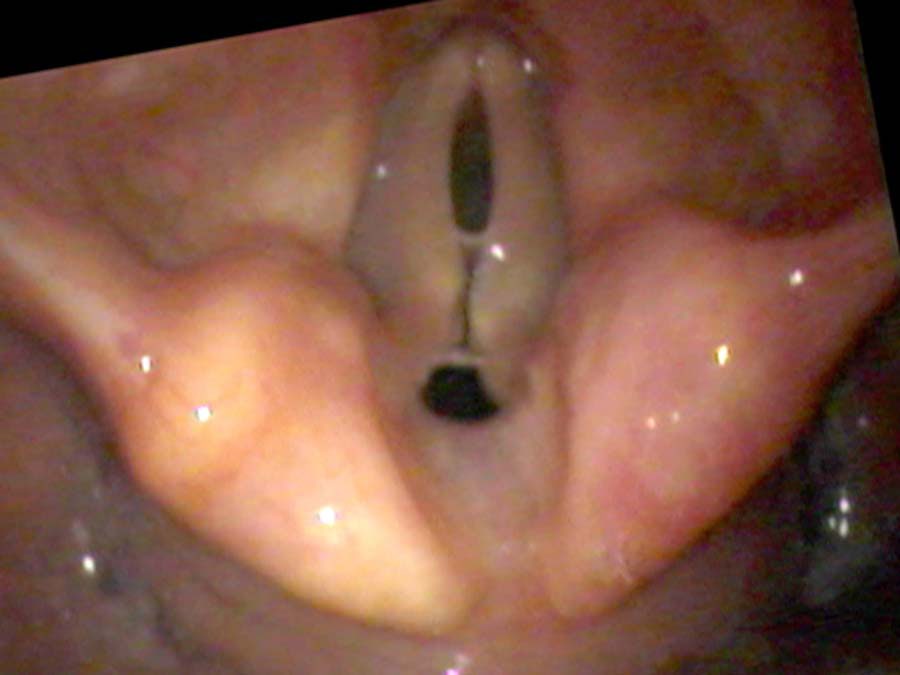

Vocal underdoers — people who rate 1, 2, or 3 on the talkativeness scale — suffer from deterioration of the thyroarytenoid (TA) muscle. The surface mucosa is fine; it is the muscle mass within the vocal cord that responds to lack of use with atrophy and loss of bulk. This is why the condition is often described as bowing — from above, the thin cords curve away from each other even when the speaker is trying to close them, leaving a characteristic spindle-shaped gap.